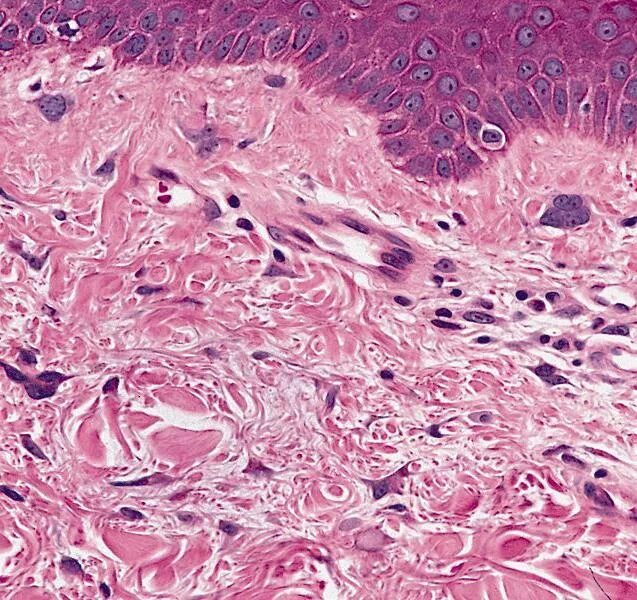

Фиброматоз мягких